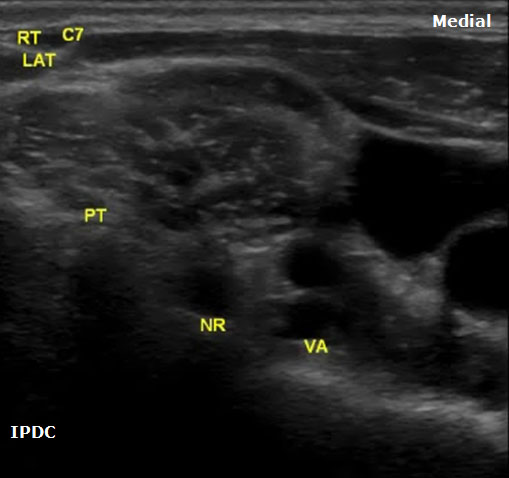

The sonoanatomy of the anterior and posterior tubercles associated with the transverse processes of the C4, C5, C6, and C7 vertebrae are used to identify their respective cervical nerve roots. The C7 vertebral body demonstrates an absent or rudimentary anterior tubercle with a prominent posterior tubercle (Figure 7). The anterior and posterior tubercles are seen as hyperechoic outlines with associated acoustic shadowing (hypoechoic area below). C6 has a sharp and prominent anterior tubercle and a shorter posterior tubercle. The nerve roots are viewed as homogeneous oval hypoechoic structures that exit through the transverse processes of the corresponding vertebral level. For example, the C6 nerve root will be seen between the anterior and posterior tubercles of the transverse process of C6 (Figures 8 & 9). The nerve roots differ in appearance from peripheral nerves below the clavicle which have a more hyperechoic appearance. As the transducer progresses to the more cephalad nerve roots, the anterior and posterior tubercles assume similar size characteristics (Figure 10) that have been referred to as the “2 humped camel sign.”[17] In approximately 90% of cases at the C7 level (Figure 7), the vertebral artery can be visualized prior to its entrance into the foramen at the C6 level.[10][18] Other important structures to visualize in the neck to assist with orientation include the thyroid, internal carotid artery, and jugular vein.

Figure 7. An axial image at the right C7 vertebral level demonstrating the prominent posterior tubercle and absent anterior tubercle. PT = Posterior Tubercle. NR = Nerve Root. VA = Vertebral Artery.